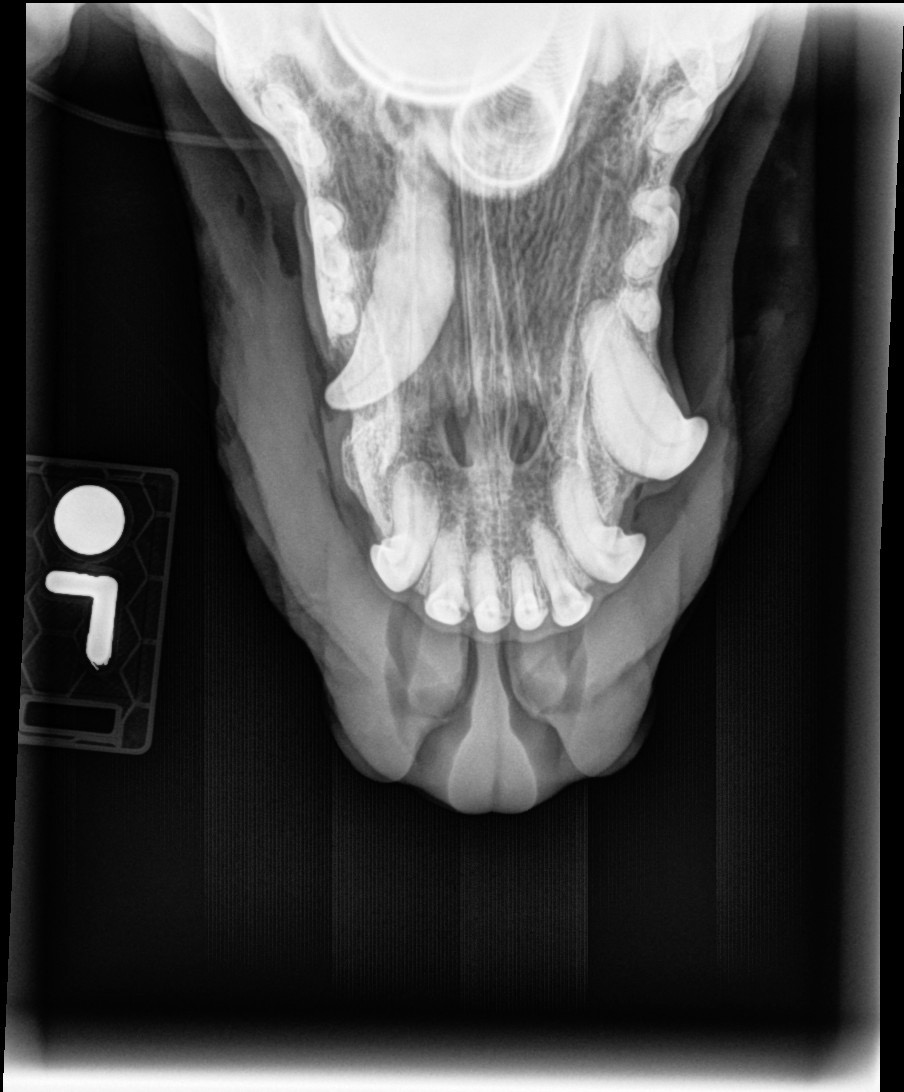

Hi! My name is Sydney, but more importantly, my dog’s name is Bailey. Last September, I adopted her in a home-to-home adoption. She came from a rural farmland next to the border of East Montana, all the way to Missoula, where she has come out of her shell by tackling her fears. She came to me as a nearly 6-year-old dog, up to date on vaccines, but had a rough puppyhood, nearly dying from Parvo. Because of this, it is suspected the Parvo caused issues with development, and she has an “unerupted” K9. This means her largest tooth on the left side has been in her jaw and nasal cavity for 6 years. As her body has attempted to get rid of it (due to decay and infection risk), she developed a drainage site both in her mouth and her nose. I noticed the site in her mouth when I got her and asked about it to the previous owners. They told me they never noticed it and it hadn’t been a concern. After 5 months of non-healing tissue continuing to decay towards her top jaw, X-rays discovered this tooth issue.

Without this surgery, the chronic inflammation will continue to destroy her jaw, soft tissues, nasopharyngeal structures, and likely cause septic infection and death over time. I did not expect this cost when adopting a cared-for adult dog, but alas, life hands us lemons. I would love to provide Bailey the life she deserves. She has only just begun living her best life.